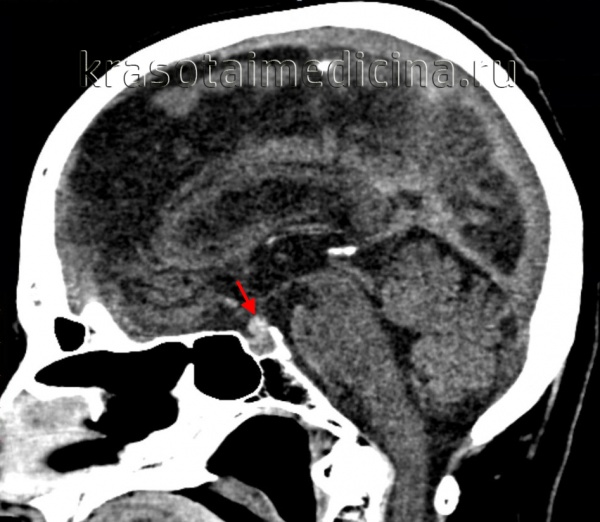

Нейровизуализацию опухоли гипофиза позволяет осуществить рентгенография черепа и зоны турецкого седла, МРТ и КТ головного мозга. Рентгенологически могут определяться увеличение размеров турецкого седла и эрозия его дна, а также увеличение нижней челюсти и пазух носа, утолщение костей черепа, и расширение межзубных промежутков. С помощью МРТ головного мозга возможно увидеть опухоли гипофиза диаметром менее 5 мм. Компьютерная томография подтверждает наличие аденомы и ее точные размеры.

При макроаденомах ангиография сосудов головного мозга указывает на смещение сонной артерии и позволяет дифференцировать опухоль гипофиза с внутричерепной аневризмой. В анализе спинномозговой жидкости может определяться повышенный уровень протеинов.

С целью визуализации аденомы проводят рентгенографию турецкого седла, которая выявляет костные признаки: остеопороз с разрушением спинки турецкого седла, типичную двуконтурность его дна. Дополнительно используют пневмоцистернографию, которая определяет смещение хиазмальных цистерн от их нормального положения.

Более точные данные могут быть получены в ходе КТ черепа и МРТ головного мозга, КТ турецкого седла. Однако около 25-35% аденом гипофиза имеют настолько малый размер, что их визуализация не удается даже при современных возможностях томографии. Если есть основания считать, что аденома гипофиза растет в сторону кавернозного синуса, назначают проведение ангиографии головного мозга.

При макропролактиномах более применимо КТ головного мозга, т. к. хорошо визуализирует костные структуры (основание турецкого седла – анатомическую область расположения гипофиза).